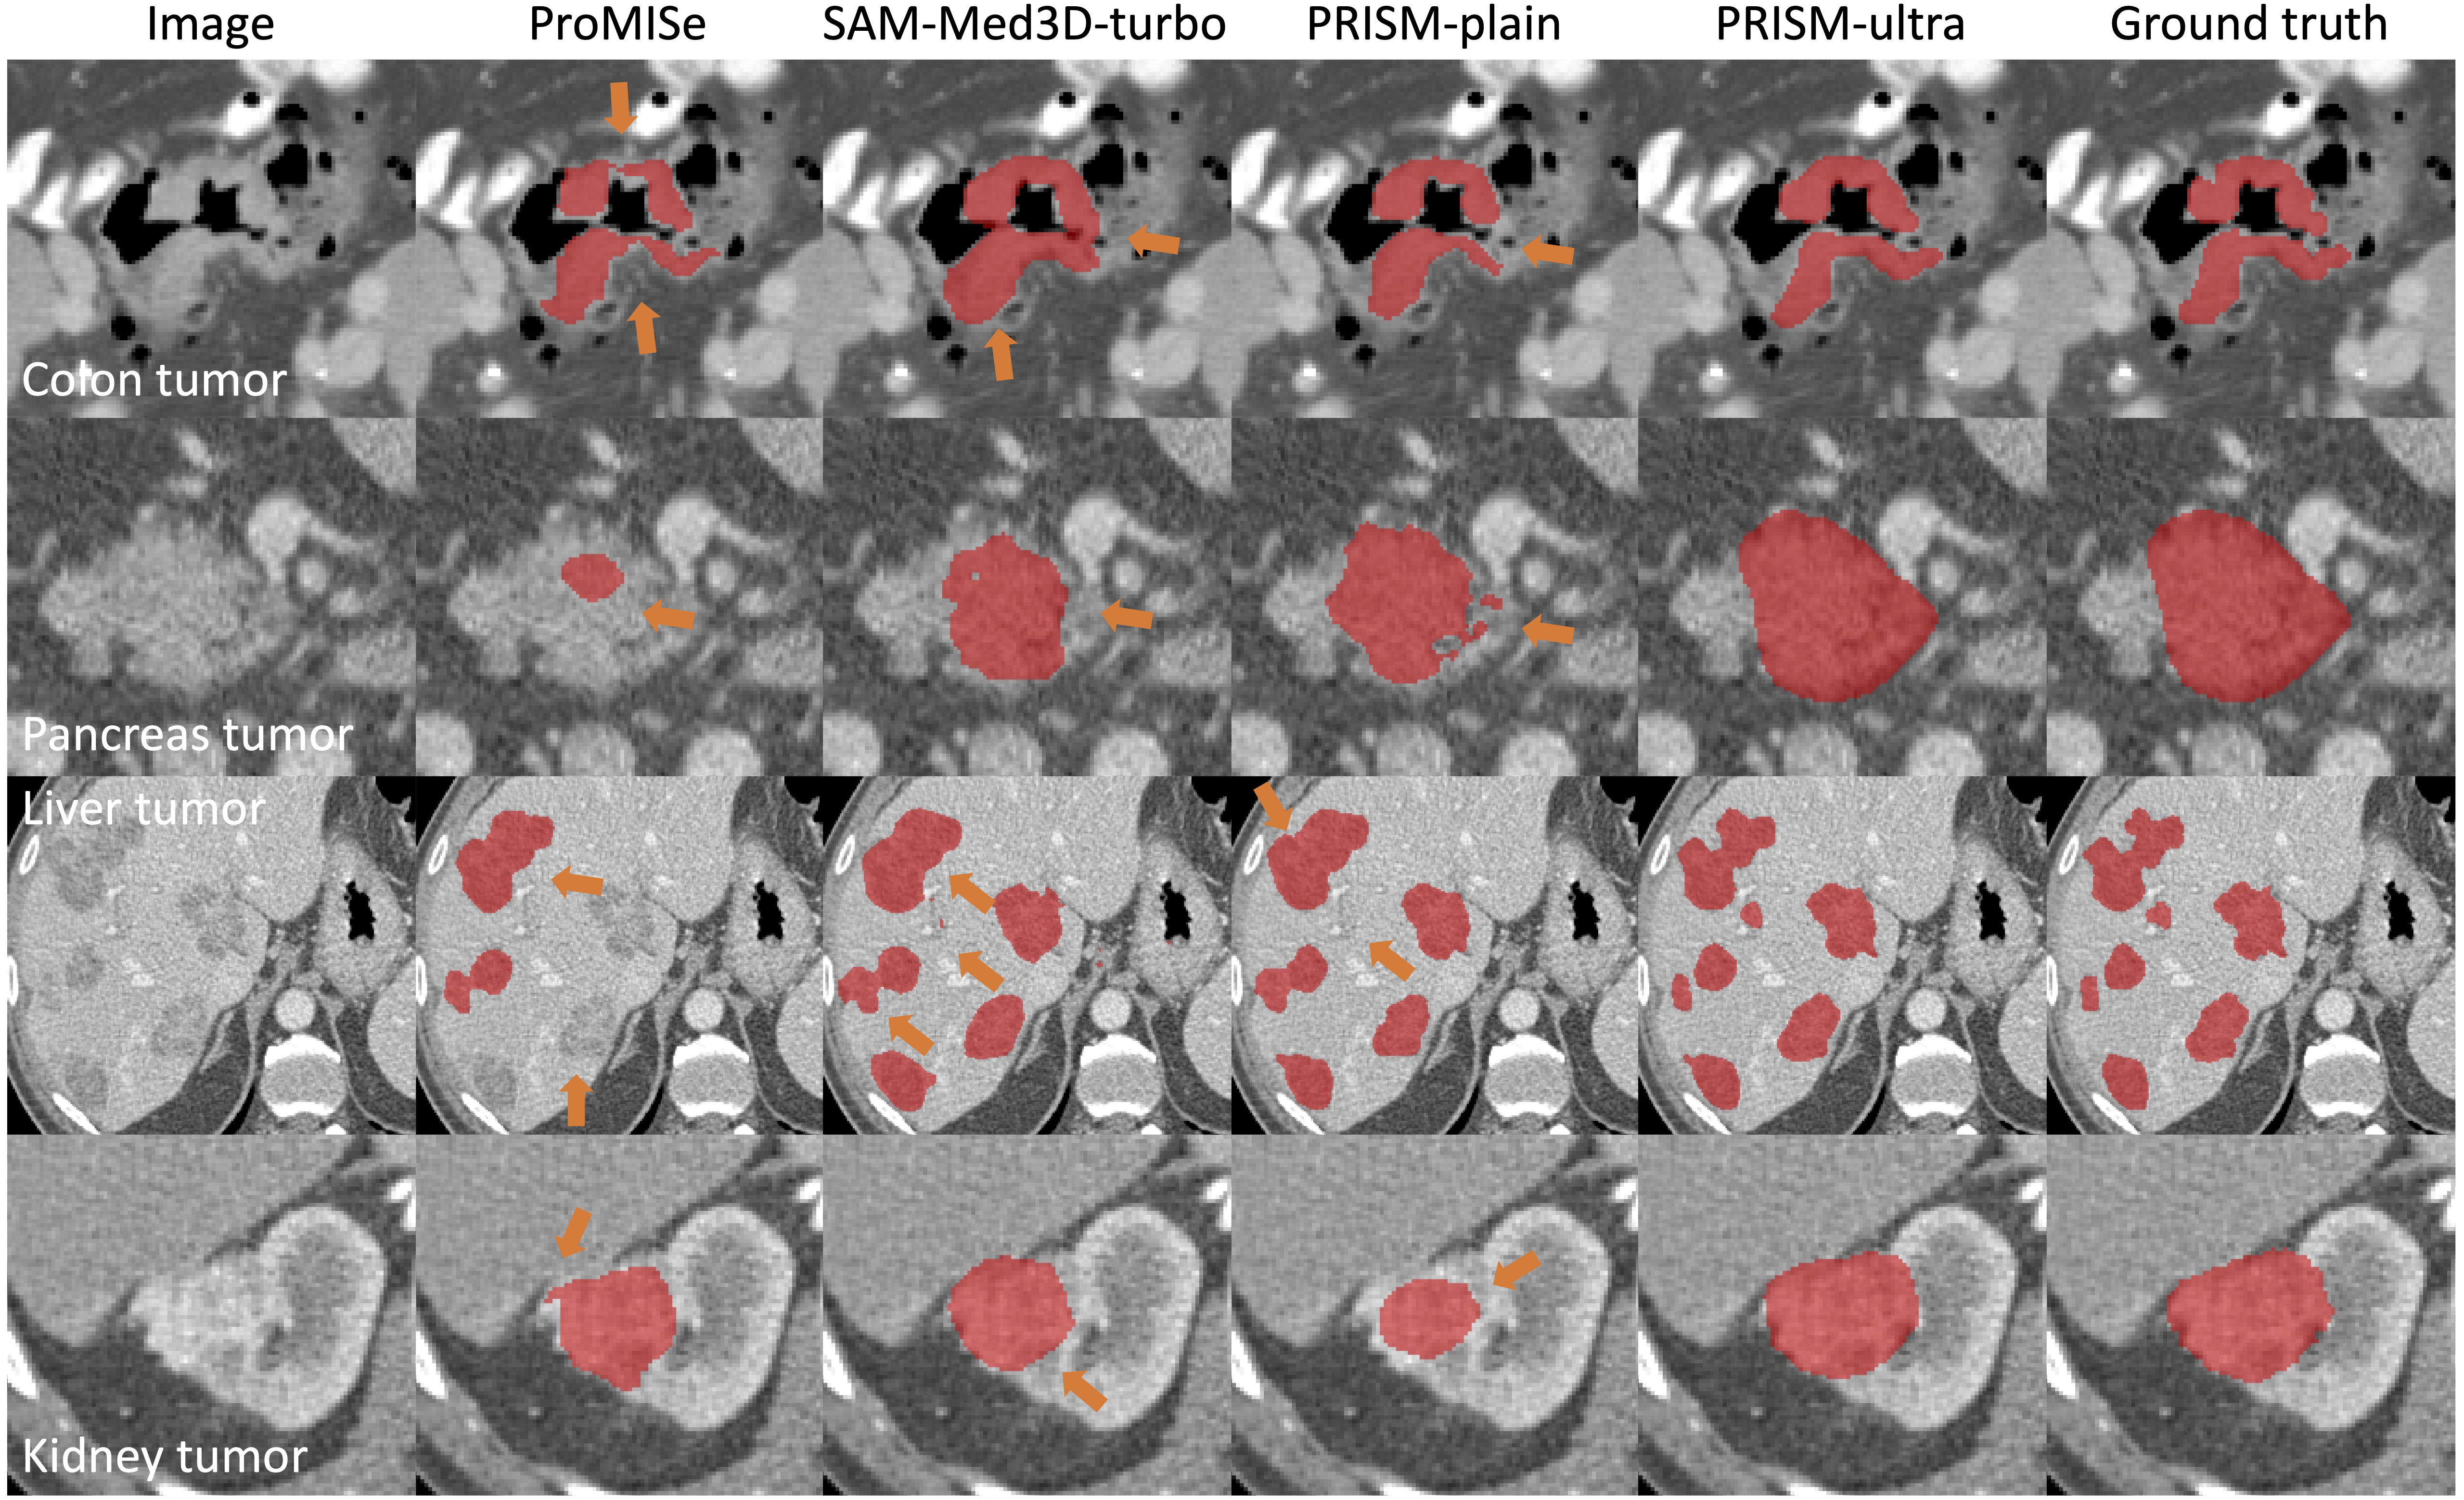

Qualitative results with compared methods qualitative_results

The quantitative results can be viewed in our paper.